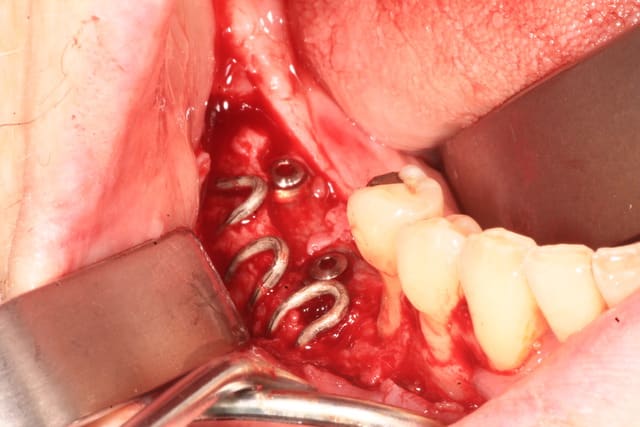

Première ré-entrée. il en manque un peu sur l'implant mésial, mais c'est plutot pas mal.

par contre, la grille est pas facile a enlever. elle s'est retrouvé enfoui dans la muqueuse, avec 1 a 2 mm de tissu en dessous.

je suis quand meme un peu déçu de ne pas avoir d'os au contact de la grille.

je ne sais pas pourquoi. la membrane collagene qui fait barriere était pourtant une membrane a résorbtion lente ( hyprosorb, de chez TLBM ).